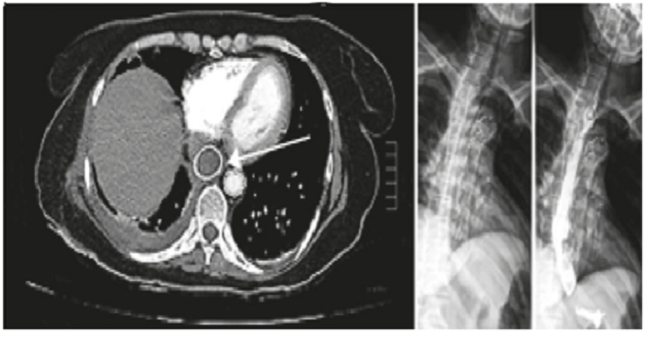

Con estos hallazgos, se inició el tratamiento con antibiótico de amplio espectro y se hizo una nueva endoscopia de vías digestivas altas. Esta demostró una solución de continuidad en la pared posterior del esófago medio, con foco de necrosis transmural de 2,5 cm2, a 29 cm de la arcada dental. Se implantó una endoprótesis recubierta de 120 x 18 mm, en posición adecuada, con su borde proximal a 25 cm de la arcada dentaria (figura 4).

Después de su egreso, se cambió la endoprótesis esofágica a una plástica totalmente recubierta (Polyflex Esophageal Stent™), con la cual permaneció por dos meses; toleró la dieta corriente y, en la endoscopia de control, la mucosa esofágica era normal. Seis meses después del egreso, se documentó el cierre completo de la fístula en el esofagograma de control (figura 5, A y B).